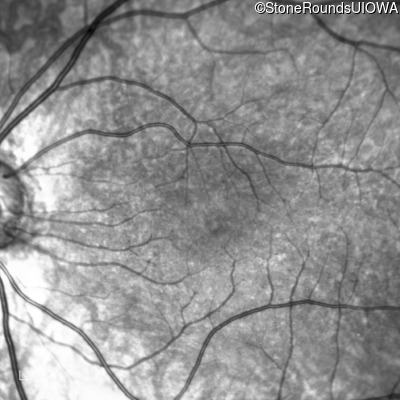

Infrared Fundus Photograph - Right - 10/160 +1 sc

Exemplar

Infrared Fundus Photograph - Left - 10/200 sc